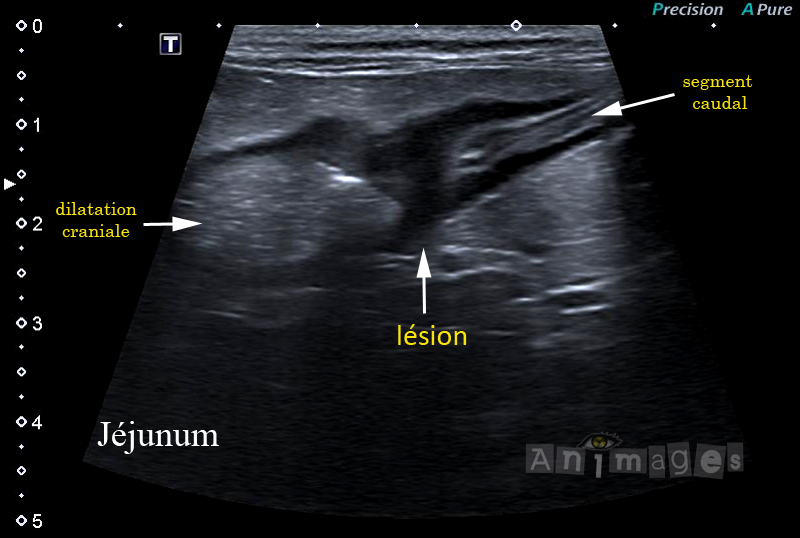

Il était une fois Benoit, un siamois mâle opéré de 11 ans, référé pour une échographie abdominale dans le but d’investiguer une perte d’appétit et une léthargie durant depuis maintenant 3 à 4 semaines, le tout ayant débuté par des vomissements projectiles. Les vomissements persistent depuis. L’examen démontre que Benoit est abattu, déshydraté et inconfortable à la palpation abdominale. Son profil sanguin n’indique alors qu’une légère anémie (HT 27%) avec une légère hausse des bilirubines totales et une légère baisse des protéines totales (alb/glob = 30/26). L’examen échographique de l’abdomen révèle, entre autres, un phénomène obstructif, impliquant le jéjunum, associé à une lésion pariétale focale, circonférentielle et sténosante (image ci-dessous). La paroi affectée est hypoéchogène et il y a perte de distinction de ses couches. Cranialement il y a accumulation d’ingesta (signe du gravier) et hypertrophie de la musculeuse intestinale indiquant ainsi une lésion chronique et progressive. Caudalement l’intestin est vide de contenu. Ces changements sont accompagnés d’une légère lymphadénomégalie régionale.